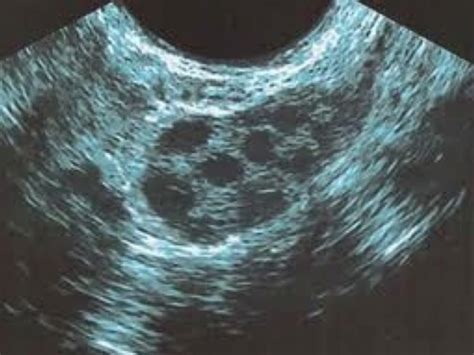

Los folículos primordiales constituyen el "stock" inicial con el que nacemos y van disminuyendo con los años. Los folículos antrales son aquellos visibles mediante ecografía al inicio del ciclo menstrual (días 2-5), midiendo entre 2 y 10 mm. Estos folículos reflejan la reserva ovárica funcional disponible en un momento dado. De este grupo, en un ciclo natural, se selecciona un folículo llamado dominante, que crece más rápidamente y se prepara para la ovulación. Los demás folículos se atresian, es decir, desaparecen.

Conocer la reserva ovárica es fundamental en el estudio de la fertilidad femenina. Actualmente, el método más fiel para estimarla es el recuento de folículos antrales por ovario, realizado mediante ecografía transvaginal en los primeros días del ciclo menstrual (días 2 a 5).